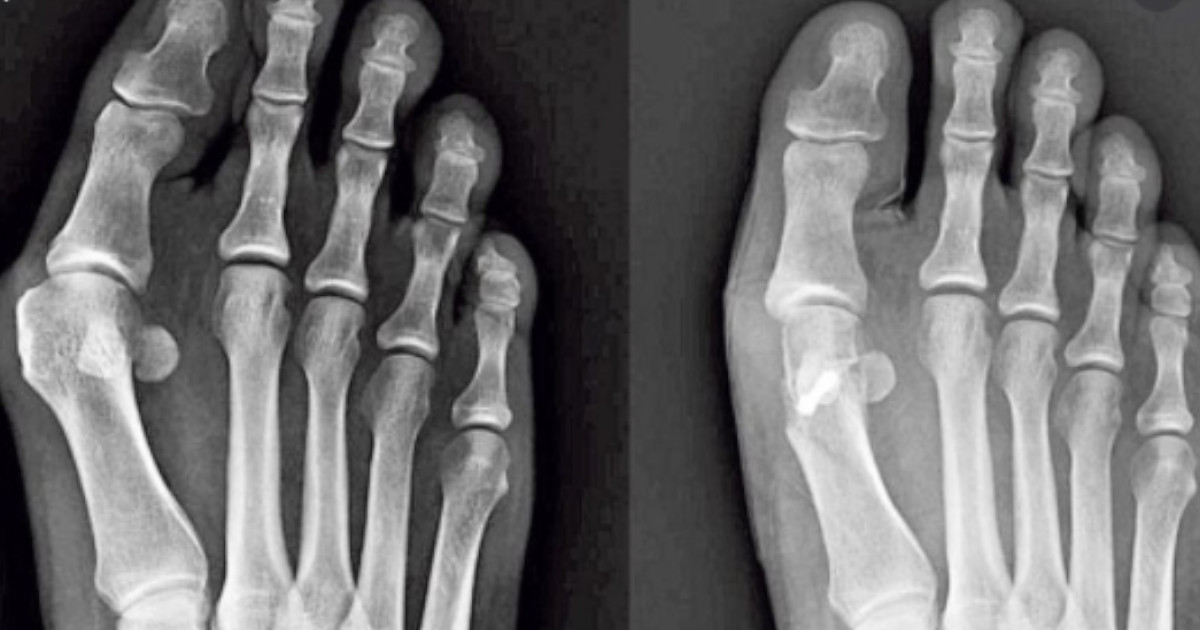

Haluks to narośl, która pojawia się z boku, po zewnętrznej stronie dużego palca u stopy, powodując jej zniekształcenie.

Wpływa na nie tylko na wygląd kończyny, ale również na codzienne funkcjonowanie osoby dotkniętej tym problemem. Co istotne, zmiany te z czasem się pogłębiają, powodując zmiany w kącie płaszczyzny stóp i przyczyniając się do ich trwałego okaleczenia. W tym artykule przyjrzymy się czynnikom, które powodują występowanie haluksów i podpowiemy, jak radzić sobie z tym schorzeniem.